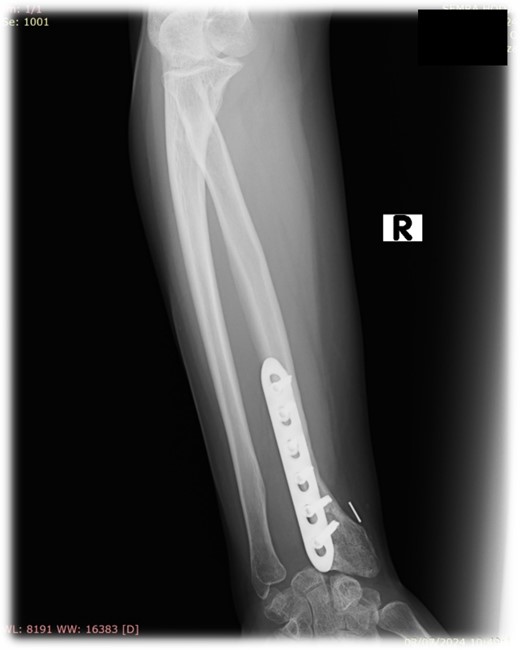

Resection of the tumor and harvesting of the bone graft from the ipsilateral proximal fibula was done simultaneously. We harvested a graft with a length of 8 cm with an inferior lateral geniculate branch and peroneal vessels to be used in the reconstruction of the defect that remained after the resection of the tumor (Fig. 2). After placing the graft in the place of the defect, the inferior lateral geniculate branch was anastomosed through a terminal-lateral anastomosis with the radial artery, while the vein was connected to the cephalic vein through an end-to-end anastomosis. The graft was fixed with a plate and screws, and two Kirschner wires (Fig. 3).

Reconstruction of the defect after resection of the GCTB of the distal radius and anastomosis of the vessels.

At 2 years follow-up, no clinical and X-ray signs of tumor recurrence or graft resorption were detected, both X-ray and CT confirmed that bone healing has been achieved (Figs 7 and 8) On physical examination, the patient has decreased wrist dorsal and palmar flexion, all other wrist movements are in normal range of motion and without pain (Fig. 9).

Follow-up X-ray of the right forearm 2 years after the surgery in profile plane

Follow-up X-ray of the right forearm 2 years after the surgery in anterior–posterior plane.